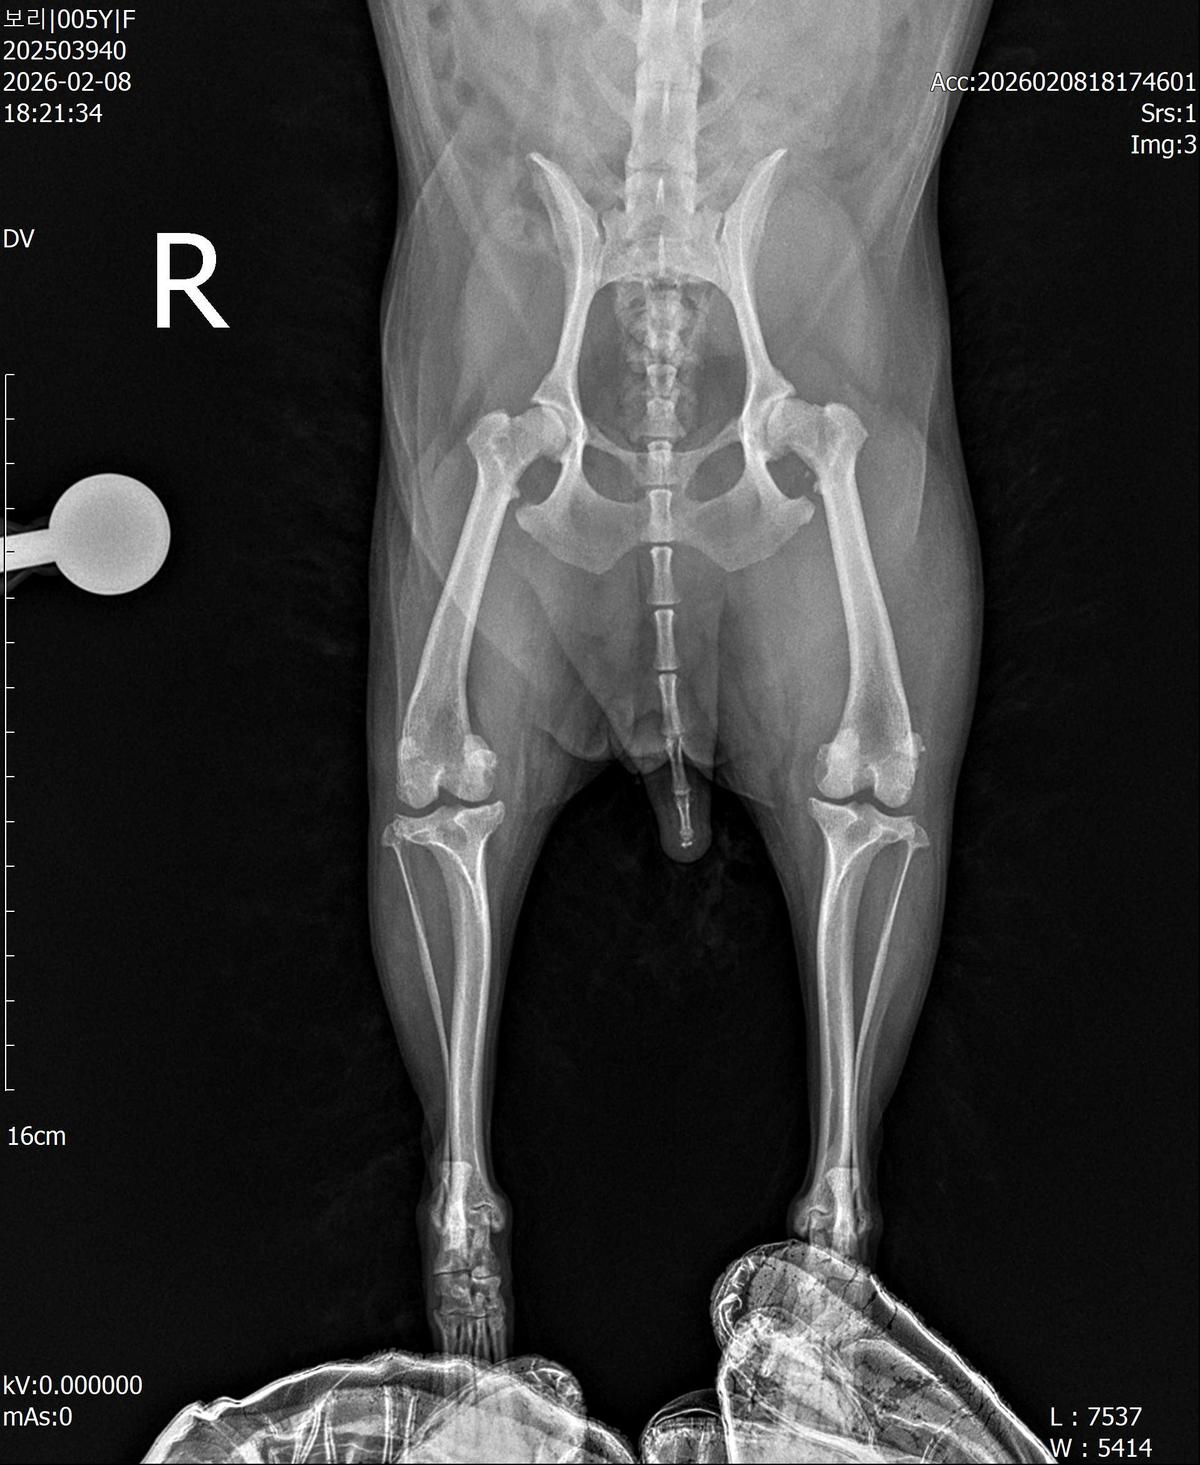

강아지 슬개골탈구 진단 받았습니다 몇군데 병원을 다녀봤는데 진단이 달라 궁금해서 질문 해봅니다 일단 저희 강아지는 오른쪽 다리를 갑자기 들고 다니고 절어 병원을 방문하게 되었고요 왼쪽은 증상이 없지만 오른쪽만 있는 상태였습니다 첫번째랑 두번째 병원에서는 슬개골 탈구 진행중이고 왼쪽이 3기 오른쪽이 2기 정도라고 했습니다 하지만 왼쪽은 아예 빠져있어 증상도 없고 아파하지도 않는다고 했고 오른쪽은 빠졌다 안빠졌다 해서 증상이 있다고 했고 십자인대가 파열된 걸론 보이지 않는다고 했습니다 그래서 양쪽 슬개골탈구 수술만 진행하면 된다고 했고요 근데 세번째 병원에서는 둘다 왼쪽이 좀 더 심한 슬개골 탈구 3기 정도라고 했고 오른쪽만 십자인대 부분파열이 보인다고 했습니다 그래서 십자인대 파열이 아닌 왼쪽은 굳이 수술할 필요가 없고 나중에 십자인대 파열이 오거나 증상이 나타나면 그때 수술하면 된다고 했습니다 그래서 오른쪽 슬개골탈구 수술과 tplo를 하는 방식으로 수술을 한다고 했습니다 여기서 궁금한점은 1. 십자인대 파열이 사진상으론 보이지 않는다고 하는데 사진상으로 알 수 있는 건가요? 2. 십자인대 파열이 아니면 슬개골탈구 수술을 굳이 할 필요 없다고 하셨는데 맞는 건가요? 3. 꼭 슬개골탈구와 십자인대 수술을 같이 해야 결과과 더 좋아지나요? 4. 사진상으로 십자인대와 슬개골 수술을 같이 해야할까요? 5. tplo 수술방법이 가장 안전하고 좋은 수술방법인가요? 6. 슬개골탈구로 인해 십자인대가 끊어지는건 아니라고 들었는데 맞나요? 슬개골 탈구 수술로 십자인대를 예방할 수 있나요?